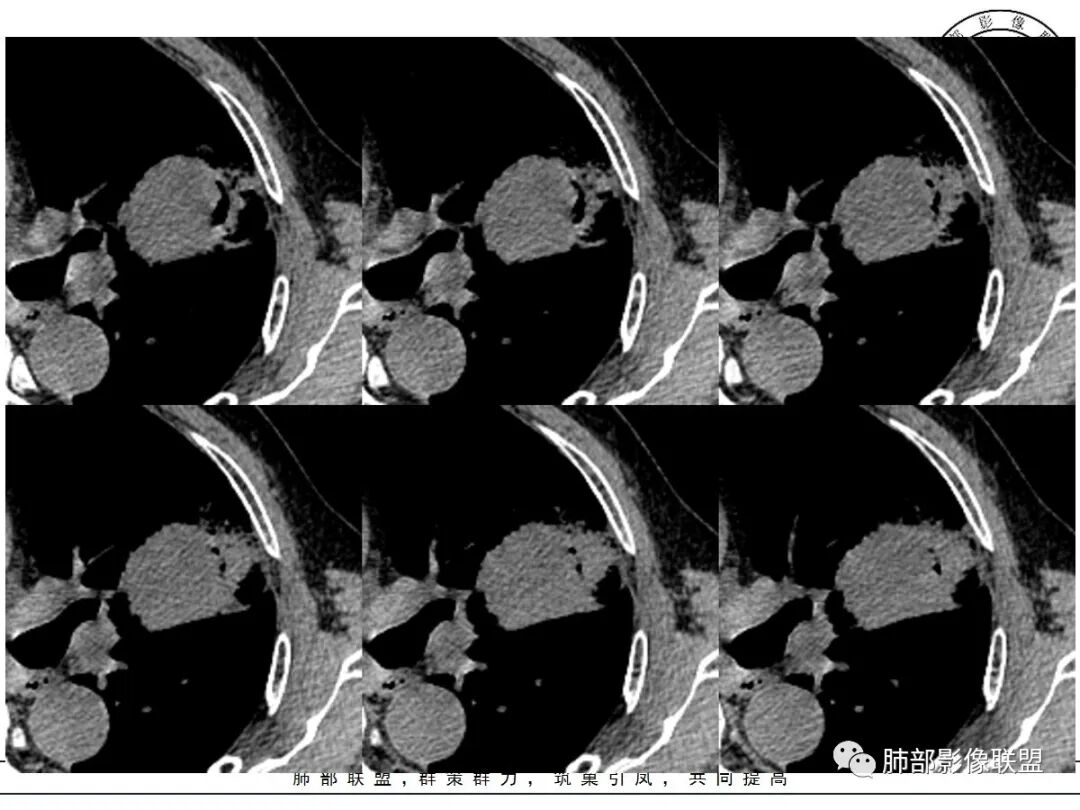

左肺上叶类圆形软组织影,边界较清楚,其内密度均匀,外侧缘可见空气新月征,并可见点状钙化,增强扫描可见均匀强化,病灶周围可见磨玻璃渗出性密度影,斜裂侧光滑平整。考虑炎性病灶,以肉芽肿性炎症为主(如真菌性肉芽肿),鉴别结核(无卫星灶,无多态性),肺癌(无毛刺,分叶等恶性征象,)细菌性炎症(密度一般不这么致密,很少钙化及空气新月征)。

左肺上叶类圆形软组织影,界清,内见空洞影,病灶周围斑片影,可见空气支气管征,未垮叶。考虑炎性病变,糖尿病四大金刚,肺克?毛霉?

老年男性,血糖升高六年,反复咳痰咳嗽3周,左肺上叶近斜裂类圆形肿块影,边缘伴磨玻璃影,边界不清。内部可见支气管走行、钙化、小空洞,叶间裂局部膨隆,增强扫描轻度强化,内部可见小的低密度区,边界尚清。考虑为炎性病变可能性大。

左肺叶裂旁实变影,宽基底与叶裂胸膜相连,边缘平直,部分略膨隆,病灶近段及上段支气管深入病灶内,部分壁略增厚,远端支气管截断,似有小空泡,壁规则,内部可见高密度钙化,周围可见模糊的GGO,血象正常,考虑结核(NTM),鉴别隐球菌,奴卡,放线菌。

老年男性,66,反复咳嗽、咳痰3月。糖尿病,血象不高。

胸部CT:左肺上叶类圆形肿块影,边界较清楚,密度较均匀,内可见小片坏死、偏心空洞、空气新月征、点状钙化,周围晕、絮状渗出、边缘模糊,支气管扩张、充气征、支气管进入病灶堵塞,叶裂牵拉明显,增强扫描中度均匀强化,纵隔可见淋巴结。考虑:炎性病灶,肉芽肿性炎症,曲霉?毛霉?鉴别:TB,淋巴瘤。

左上肺类圆形肿块影,边界较清楚,支气管通畅略扩张,周围磨玻璃影,其内密度均匀,外侧见空气新月征,且见点状钙化。叶间裂光滑稍膨隆。老年男性,糖尿病,高血压,痰培养克雷伯菌。综合考虑炎性病灶,克雷伯合并真菌感染,曲霉。结核合并真菌。鉴别肺癌合并感染。

左肺上叶类圆形软组织影,边界稍模糊,其内密度均匀,外侧缘可见空气新月征,并可见点状钙化,增强扫描渐进性强化,病灶周围可见磨玻璃影,斜裂侧光滑平整,气管未见明显闭塞,淋巴结未见肿大,糖尿病患者,首先考虑感染性变,结核并曲霉?

1、团片状,实行密度区外观整体圆顿,位于上叶尖后段与下舌段区间。局部膨隆,但未见分叶,肿瘤多见。

2、偏心空腔病灶,气腔略呈新月形,壁不规则,腔内结节相对密实,明显强化且不均,支持新生物而非曲菌球等。炎性空洞多有强化环。

3、病变强化较明显,其内隐约显示多发小斑片状无强化灶,可疑边界不清小灶坏死区。病灶内血管影浅淡、模糊不规则。

4、支气管改变:上舌段支气管远段延入部分稍示僵硬。尖后段见分支支气管阻塞,恶性多见。

5、周围磨玻璃,3个月后逐渐转为密实,应符合当初附壁生长为主,且逐渐向实体成分转换。

6、病变长轴平行且受限于胸膜,外围大内带小,符合外朝内发展病变。“腔内结节状明显强化”加之支气管改变有力支持新生物诊断。如此大范围边界不清的磨玻璃影让人浮想联翩。如此大范围病灶,肺门纵隔未见肿大淋巴结也让人意外。